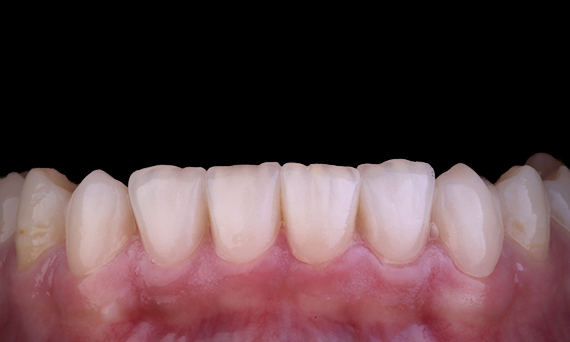

Amélogenèse imparfaite

Restauration complète de la bouche avec 28 restaurations tout céramique

Un cas particulier et prolongé de malocclusion squelettique de classe II et d’amélogenèse imparfaite généralisée chez un adolescent a été référé pour une réhabilitation prothétique. L’objectif du traitement était de préparer la structure dentaire restante, d’éliminer les contre-dépouilles et de faire de la place pour des couronnes entièrement en céramique couvrant toute la dentine et simulant l’émail perdu.

Avant : Situation initiale avant le traitement orthodontie.

Après : Résultat final, 1 semaine après l’opération.

Alexander Declerck, (DDS, MSc)

Laethem-Saint-Martin, Belgique